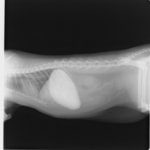

主訴:2日前の夜に桃の種を飲み込んだとのこと。元気・食欲に問題はなく、嘔吐などの消化器症状もみられなかった。誤飲した当日に他院にて催吐処置を試みたが、吐き戻さなかったとのこと。

単純レントゲン検査:明らかな異常所見なし

消化管バリウム造影レントゲン検査:胃内にて異物の存在を疑う異常所見を認めた。

造影直後

内視鏡検査:内視鏡下にて、バスケット鉗子を用いて胃内異物を摘出。

異物内容:桃の種 (約4cm大 写真上)、とうもろこしの芯 (約2.5cm大 写真下)

本症例は、床に落としてしまった桃の種を誤飲していました。動物の体格に対して異物が非常に大きく、開腹手術となる可能性があった症例でした。また、桃の種と一緒に出てきたとうもろこしの芯は、日々のおやつとして与えていたものということでした。とうもろこしの芯は非常に硬く、小さく切って与えても消化されず、長期間胃内に残ってしまうことや腸閉塞の原因となる為、注意が必要です。